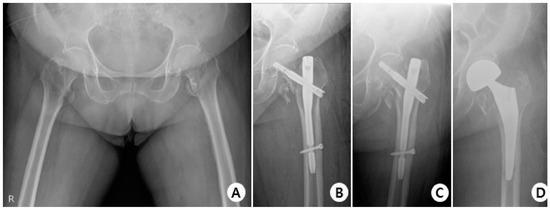

In the Affixus group, there were 34 cases with no complications, 5 cases of cut-out (Figure 5), 1 case of cut through, 4 cases of non-union, 1 case of delayed union, and 1 case of osteolysis.

Figure 5.

(A) Total hip AP X-ray of a 77-year-old female diagnosed with an intertrochanteric fracture of the left hip. (B) Immediately post-operation, reduction was performed using the Affixus hip fracture nail, but there appeared to be a mismatch in rotation. (C) The postoperative six-month X-ray shows reduction loss and the progression of varus deformity, with the lag screw experiencing cut-out. (D) X-rays show the revision surgery performed with arthroplasty.

There was no statistically significant difference in the occurrence of complications between the two groups, and neither group experienced implant breakage (Table 7).